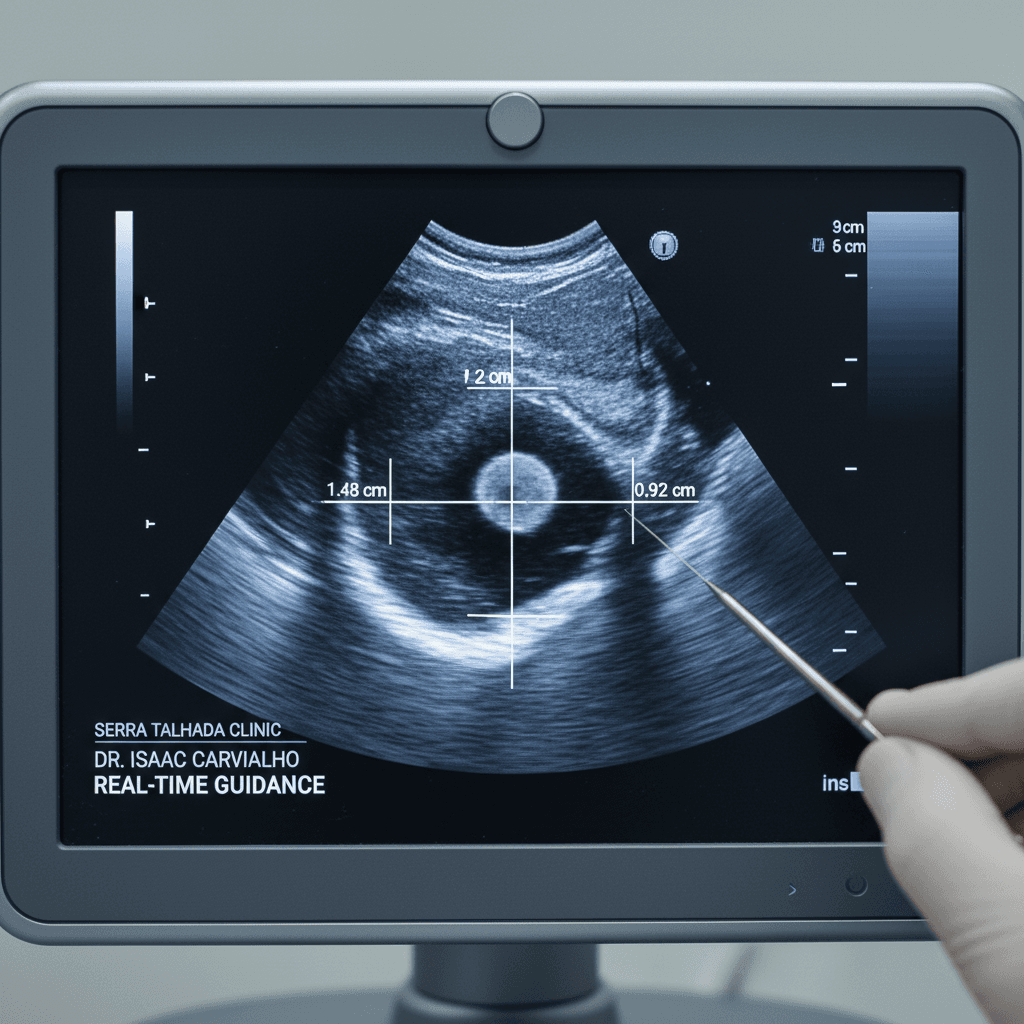

Dr. Isaac Carvalho realiza biópsias com precisão em Serra Talhada. Cada procedimento é conduzido pessoalmente pelo especialista com visualização em tempo real.

Visualize os procedimentos de biópsia realizados pelo Dr. Isaac Carvalho com orientação ultrassonográfica em tempo real para diagnósticos precisos.